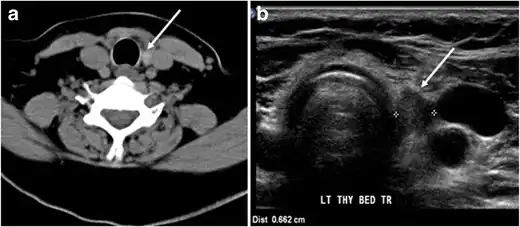

Fig. 2. A 51-year-old female patient post left hemithyroidectomy, with incidentally discovered a right thyroid colloid nodule on CT scan. an Enhanced axial CT scan of the neck demonstrates a well-defined, hypodense right thyroid nodule (white arrow) with no internal calcifications or cervical lymphadenopathy. b Transverse greyscale thyroid ultrasound demonstrates a well-defined, hypoechoic right thyroid lobe nodule with a central echogenicity including comet tail (ring down) artefacts (white arrow). No vascularity (not shown) or calcifications were detected.